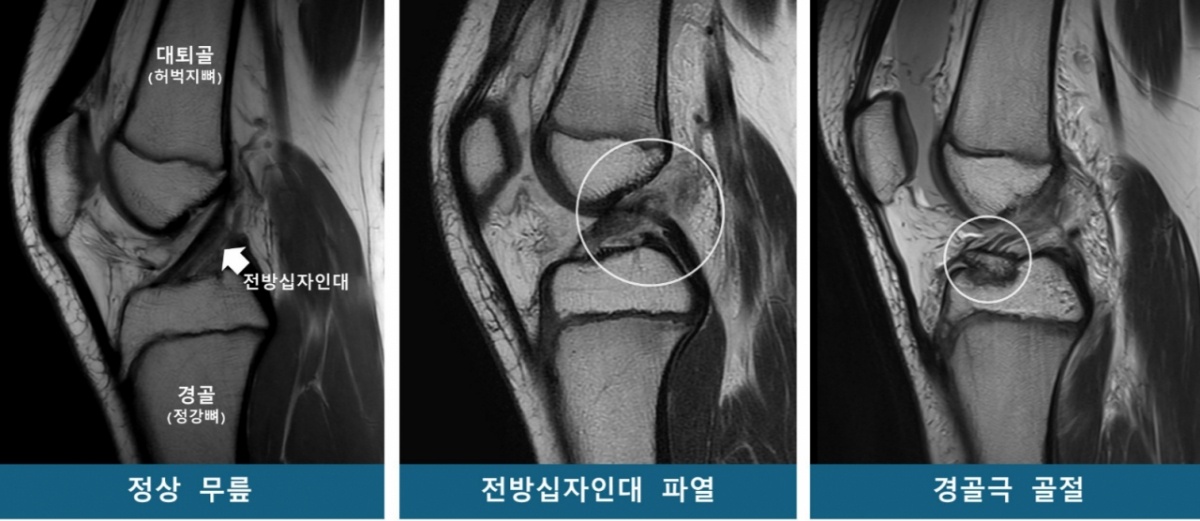

연구팀은 소아청소년을 53명씩 ▲전방십자인대 파열군 ▲경골극 골절군 ▲대조군(정상 무릎)으로 구분하고 연령·성별을 매칭했다. 이후 MRI를 재구성한 3차원 영상을 바탕으로 14개의 해부학적 지표를 분석했다.

소아청소년은 뼈와 근육 발달이 미성숙해 스포츠 손상에 취약하다. 특히 '전방십자인대 파열'과 '경골극 골절'은 소아청소년에게 발생하기 쉬운 대표적인 무릎 손상이다. 같은 외상을 입어도 어떤 환자는 십자인대가 파열되고, 다른 환자는 경골극 골절이 발생하는데, 이처럼 서로 다른 손상이 발생하는 원인은 명확지 않았다. 이에 이번 연구 결과는 무릎 부상 위험이 높은 소아청소년을 선별하고, 개인별 맞춤 치료 지침을 마련하는 근거가 될 것으로 기대된다.